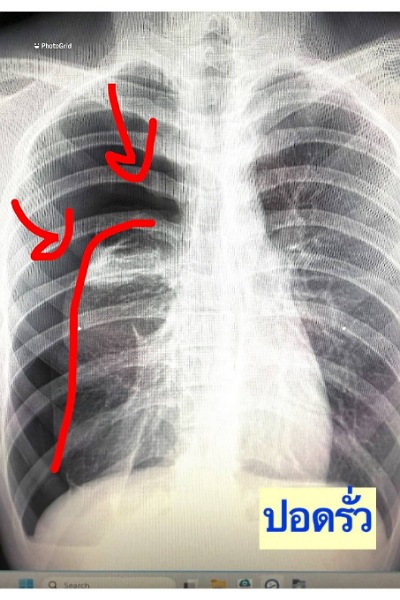

เมื่อไม่นานมานี้ ผมได้เจอเคสผู้ป่วยหญิงอายุราว 40 ปี มารักษาด้วยอาการเจ็บแน่นหน้าอก เป็น ๆ หาย ๆ อยู่หลายครั้ง แต่ไม่รู้สึกเหนื่อย รู้สึกว่าเมื่อมีอาการเจ็บหน้าอกทุกครั้ง มักจะเป็นในช่วงขณะมีประจำเดือน จึงมีอยู่ช่วงหนึ่งมีอาการเจ็บหน้าอกมากจึงรีบมาพบแพทย์ที่โรงพยาบาล หลังจากการตรวจสอบเอกซเรย์ พบว่าเป็นโรคลมรั่วในเยื่อหุ้มปอด ซึ่งมีโอกาสเสียชีวิตสูงหากไม่ทำการรักษา จึงรีบรับการรักษาตัวเข้าโรงพยาบาล

รศ.นพ.ศิระ เลาหทัย แพทย์ผู้เชี่ยวชาญศัลยศาสตร์ ทรวงอกเฉพาะทางด้านการผ่าตัดส่องกล้องในช่องทรวงอก โรงพยาบาลวชิรพยาบาล กล่าวว่าจากการวินิจฉัย ส่วนมากการทำ X-Ray หรือ ทำเอกซเรย์คอมพิวเตอร์ (CT Chest) หรือ MRI อาจพบได้ แต่อย่างไรก็ตามยังไม่มีการตรวจใดมีประสิทธิภาพที่สามารถวินิจฉัยโรคนี้ได้โดยตรง โดยในบางรายอาจพบถุงลมบริเวณยอดของปอดร่วมด้วยได้ (Lung Bleb) ในส่วนของการรักษาในโรคลมรั่วในเยื่อหุ้มปอดนี้ ประกอบด้วย 2 อย่าง ได้แก่1)การรักษาด้วยการผ่าตัด(ส่องกล้อง) และ2)การรักษาด้วยยา